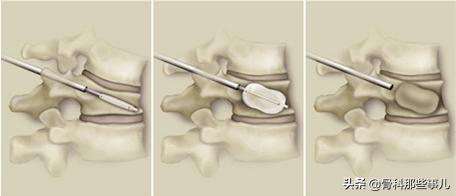

2,对于压缩程度比较重,或者疼痛剧烈,无法忍受;以及不稳定的椎体骨折,建议采取微创的手术方法进行手术治疗,这种方法称为“椎体成形术”,英文缩写PVP,或者PKP(步骤略复杂)。这种手术的大致步骤是通过X光透视定位后,用穿刺针从背部穿入骨折的椎体,向椎体内注射一种叫做“骨水泥”的材料。这种材料可以在一刻钟左右完全凝固,达到很好的止痛效果并支撑骨折的椎体。创伤很小,可以局麻手术。手术后第二天就可以下地活动,有很好的止痛效果,并且不需要卧床,避免了卧床并发症的风险。

PVP手术,骨水泥快速凝固,起到支撑和镇痛的作用

PKP手术,与PVP相比,多一个利用气囊撑开的步骤,可以对压缩的椎体进行复位